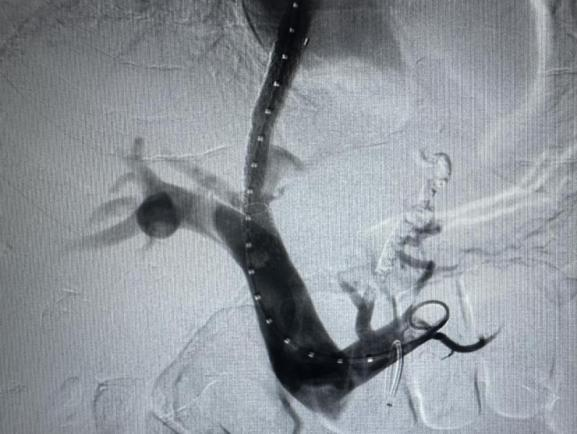

李建军主任医师表示,TIPS技术,以微创方式经患者颈静脉穿刺,在X射线引导下由肝静脉直接穿刺肝内门静脉支,在门静脉至肝静脉间建立门-体静脉人工血流通路并置入支架,从而降低门静脉压力,控制和防止消化道出血、促进胸、腹水吸收。与外科治疗门脉高压分流术或断流术相比,TIPS创伤小、并发症少、死亡率低、适应症范围更广泛。TIPS为四级手术,该技术是目前介入治疗中技术含量最高、手术难度最大的手术之一,被称为介入放射学的“皇冠”。